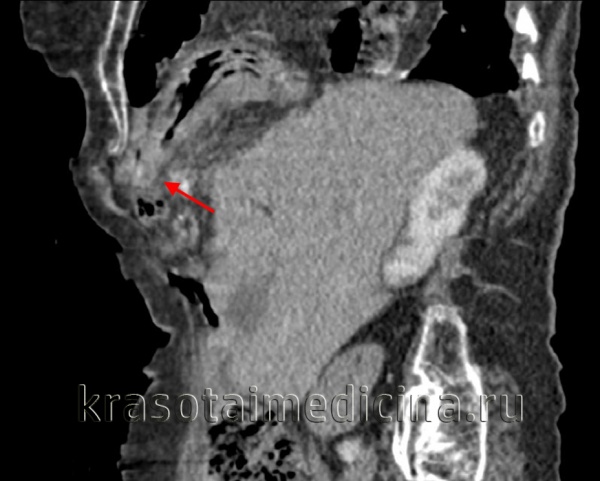

КТ органов грудной клетки/брюшной полости. Травматический дефект в передних отделах диафрагмы справа с эвентрацией кишечника, сальника, кровеносных сосудов в грудную полость